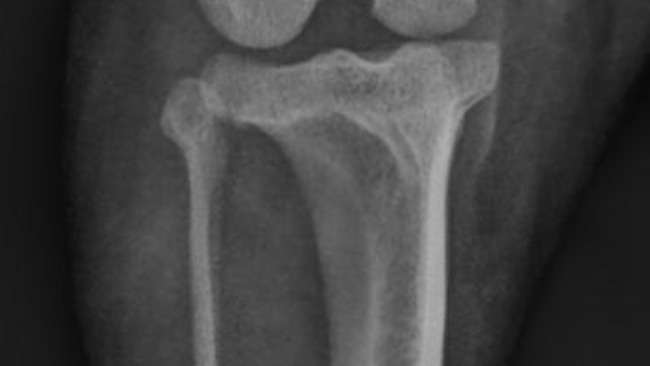

Gomez ma już za sobą dwie poważne operacje — dzielnie zniósł wszystko, mimo trudnych chwil i wielu ograniczeń. Każdy dzień to walka o jego sprawność, komfort i powrót do normalności.